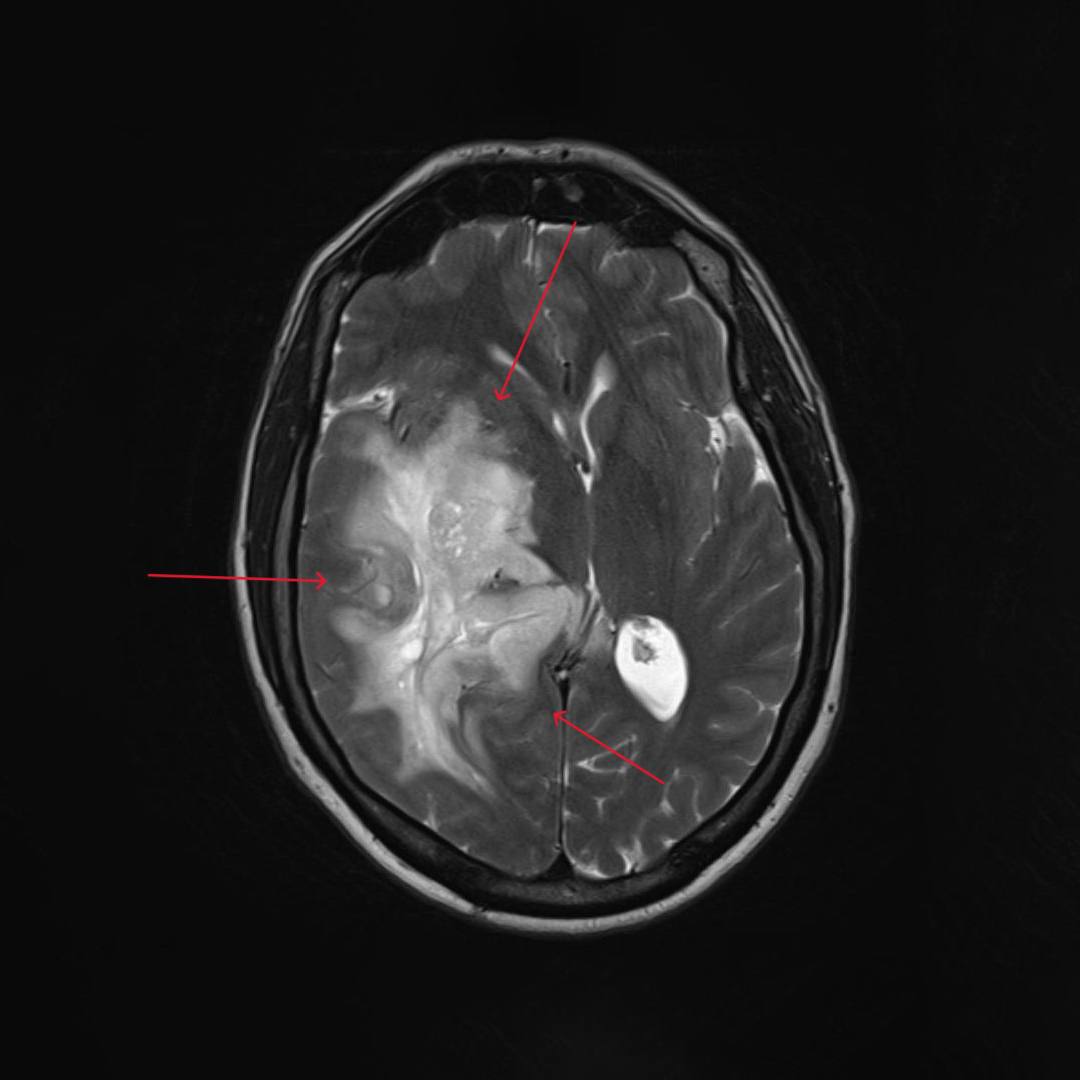

При проведении МРТ головного мозга выявлена опухоль правой височно-теменной области с переходом на островок, вовлечением базальных ядер справа и мозолистого тела с выраженным перифокальным отеком с дислокацией срединных структур мозга влево, компрессией правых бокового и третьего желудочков, среднего мозга.

При введении контрастного препарата визуализировался участок интенсивного кольцевидного накопления по периферии кистозного компонента опухоли.